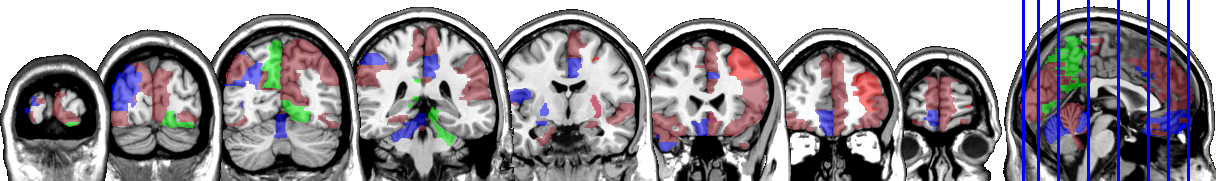

One motivating example for our methods is the application to the functional magnetic resonance imaging (fMRI). The dataset consists of the functional signals of the brain activities measured by blood-oxygen-level-dependent (BOLD), which detects hemodynamic changes based on the metabolic demands followed by neural activities. There are pre-specified regions of the brain, and the BOLD signals associated with multiple voxels in each region are integrated into one signal for that region. Thus, the fMRI data are considered to be multivariate functional data in which each functional predictor represents the signals from a region of the brain. In Section 8, we regress the ADHD index to the regional BOLD activities of the fMRI of the human subjects. There are regions of the brain in the data, and our methods reduce the regions to 41 regions with significantly lower errors than the linear functional regression. Figure 1 displays the regions of the brain’s atlas that are identified by our method. It shows that the methods simplify the data analysis and provide clear representation while keeping the crucial information. The analysis shows that there is an urgent need for new methods in the fields of medical and life sciences as well as other related areas.

In Figure 4 and Figure 5, we display the regions associated with the estimated active sets for IQ and ADHD by the MFG-LASSO respectively. The final active sets of the algorithms were extracted, and matched with the AAL’s atlas where each of the regions has a label. The regions were manually entered into the WFU picked atlas Maldjian and et al. (2003) tool of the SPM-12 ran on MATLAB 2020b to produce mask.nii files. The mask files were imported on MRIcron software to produce the multi-slice images.

The active sets cover the regions associated with IQ in Yoon and et al. (2017) such as cerebello-parietal component and the frontal component. It is mentioned in the paper that the parietal and the frontal regions are strongly associated with intelligence by maintaining a connection with the cerebellum and the temporal regions. The shaded areas cover the ones mentioned in Goriounova and Mansvelder (2019) as well. We provide the name of the regions associated with these active sets in the appendix.

It is interesting that ADHD and IQ have a large proportion of common active sets. For instance, when MFG-LASSO is applied, they overlap in ROIs where the size of active sets are and for IQ and ADHD respectively. On the other hand, the ROIs that are associated with ADHD but not with IQ are the middle and superior frontal, the Parahippocampal, the inferior parietal, and the superior temporal pole gyri. The ratio of the number of right hemisphere regions to the left ones associated with IQ is significantly greater than that of ADHD.